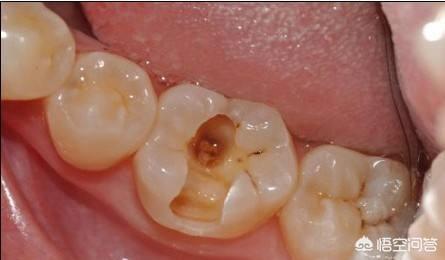

一般情况下牙齿有龋齿、牙根暴露、牙齿磨耗、牙齿劈裂等等容易造成刺激性疼痛。